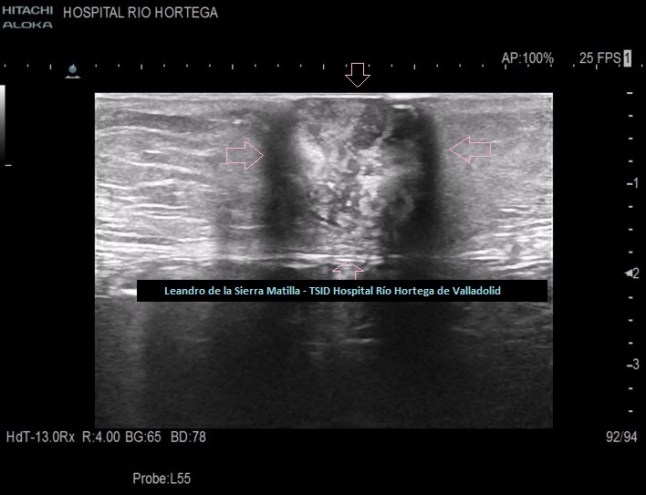

Cambiamos a una sonda lineal para un estudio más detallado, observando una LOE hipoecogénica con zonas híper-isoecogénicas, heterogénea, sólida, sin contenido de asas intestinales ni de grasa, con bordes mal definidos y con flujo doppler en su interior, ubicada dentro de la cavidad umbilical (FIGURAS 5, 6 Y 7)

5

6

7